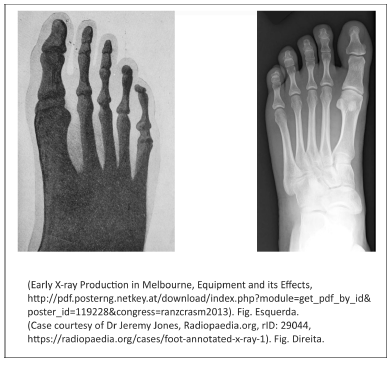

A figura da esquerda representa a primeira radiografia obtida na Austrália, em 1896, usando um tubo de raios catódicos de Crookes. A radiografia da direita é mais recente e evidencia a diferença de qualidade de imagem que se obtém hoje.

I. Os raios X não são idênticos aos raios catódicos, mas são produzidos pelos raios catódicos quando estes incidem na parede de vidro dos tubos de descarga de Crookes, utilizados na época da descoberta dos raios X.

III. A produção de imagens melhores (como a da direita) foi acompanhada por avanços tecnológicos que melhoraram a proteção radiológica de pacientes e trabalhadores ao lidar com tubos de raios X; entre eles, estão o cabeçote metálico do tubo e a tela intensificadora de imagens.